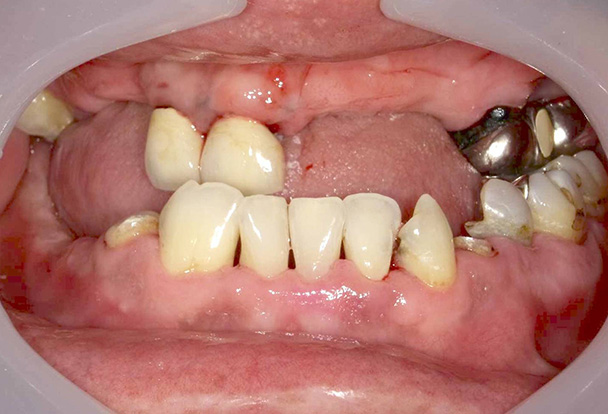

- 短期集中治療による治療例②

-

治療本数:12本

治療回数:3回■治療前(上の歯)

↓ ■治療前(下の歯)

↓ ■治療後(上の歯)

■治療後(下の歯)